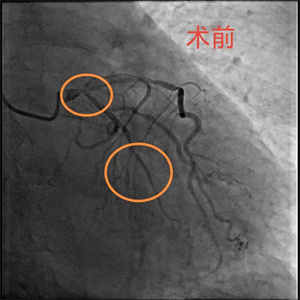

患者,李大爷(化名),76岁,因突发胸痛被家属送至我院急诊科,经完善心电图等检查后,被诊断为急性心肌梗死,随后,病人迅速被送至导管室。完善冠脉造影检查后,患者血管显影结果不容乐观,考虑左主干真性分叉合并三支病变,即右冠慢性闭塞、回旋支急性闭塞、前降支严重狭窄伴钙化。与此同时,患者出现血压、氧饱和度下降的情况,病情极其危重,随时面临死亡风险,已无法耐受及等待外科搭桥手术,急需急诊介入治疗。